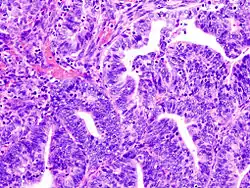

Anatomía patológica

La histopatología del cáncer endometrial es altamente diversa. El hallazgo más común es el adenocarcinoma endometrial bien diferenciado, el cual está compuesto por numerosas glándulas pequeñas, congestionadas con variados grados de atipia nuclear, actividad mitótica y estratificación. A menudo está situado en un fondo de hiperplasia endometrial. Los francos adenocarcinomas pueden distinguirse de la hiperplasia endometrial por el hallazgo de una clara invasión del estroma o por glándulas muy juntas (espalda-a-espalda) los cuales representan el reemplazo no destructivo del estroma endometrial por el cáncer. Con la progresión de la enfermedad, el miometrio llega a ser infiltrado.[11]